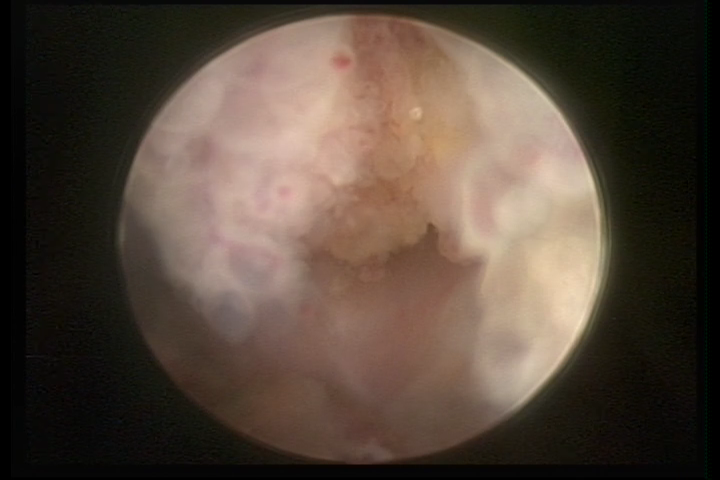

It may present a variable range of macroscopic aspects, with a pseudolopypoid aspect; resembling cerebroid tissue or presenting a decidual reaction; superficial vascularization is more evident presenting vessels in the shape of corkscrew or spirals also viewing the vascularization with atypias, with an increase on the thickness of the superficial vessels, tissue in necrosis and small dendrites (papillomatous) may be found.